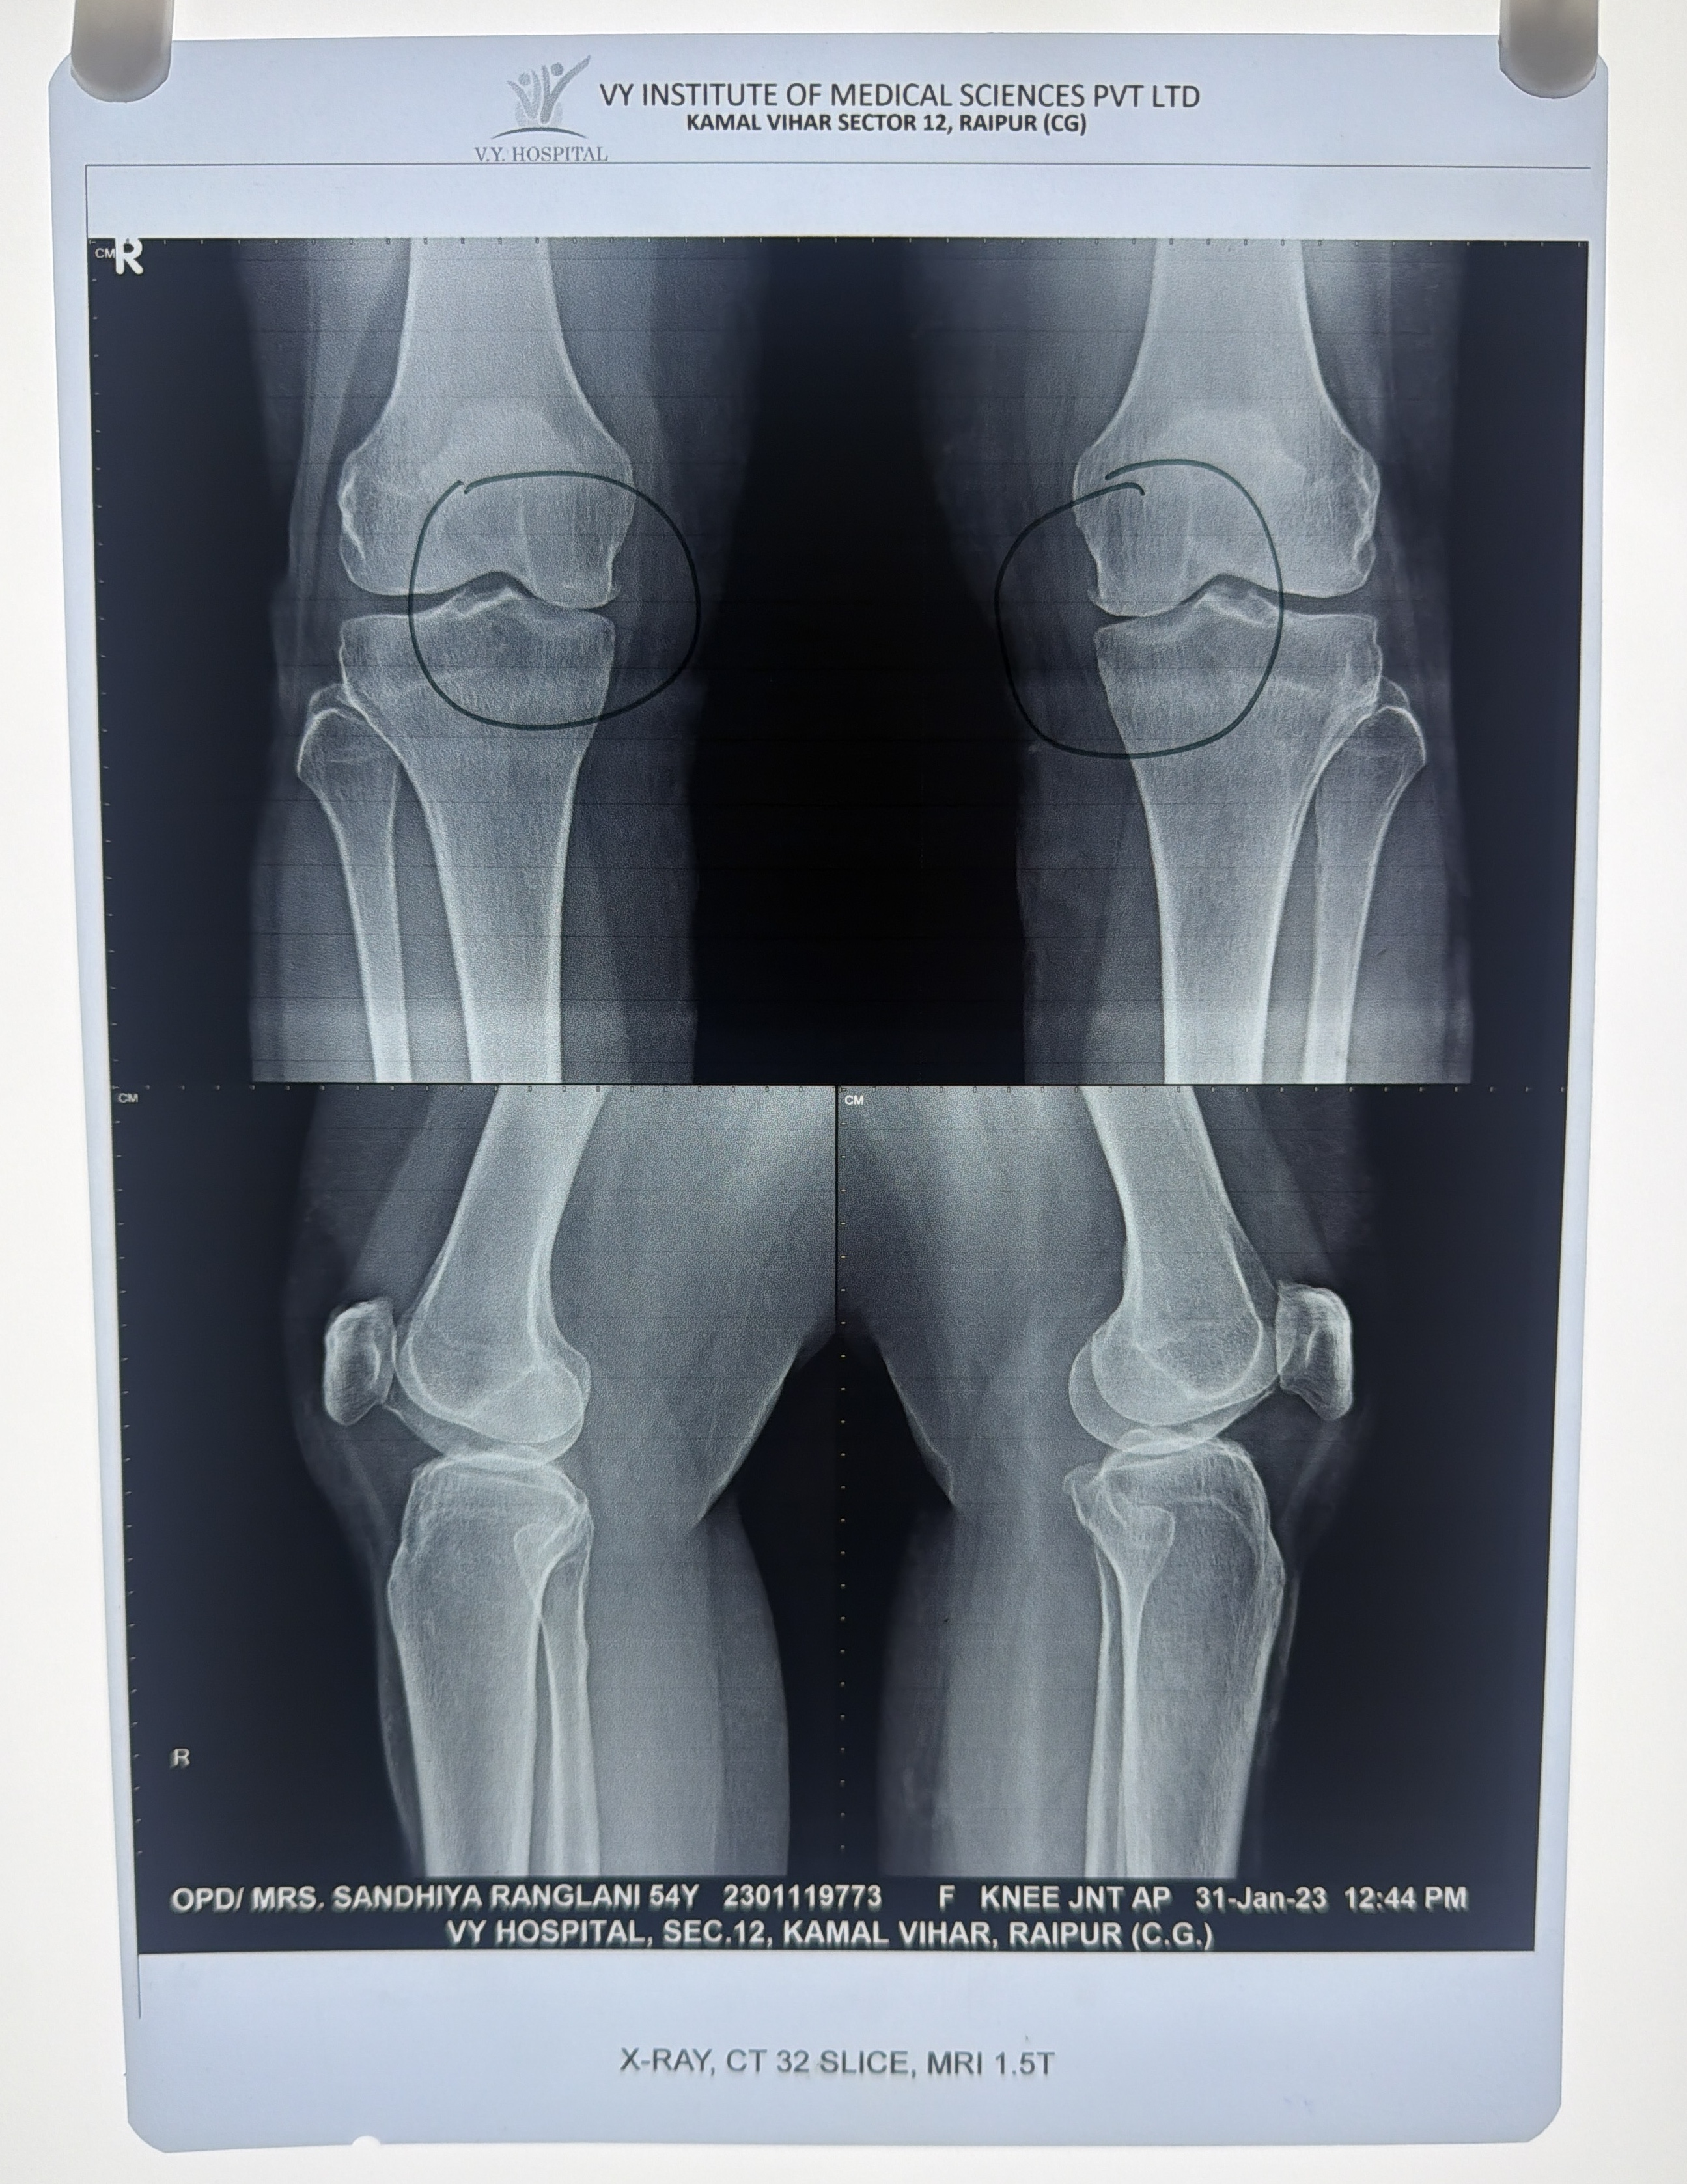

Sandhya Ranglani (Khairagarh-CG)

Before Before After After

Osteoarthritis Knee